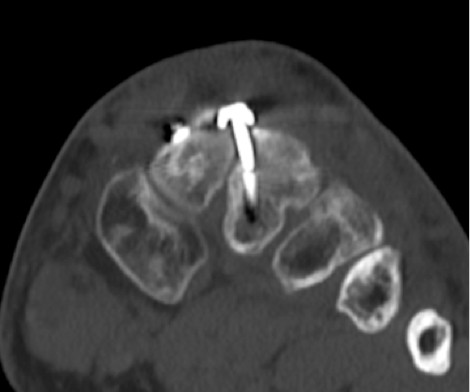

Im CT vom September 2017 ergab sich noch kein Durchbau der Arthrodesen, aber ein Bruch der das TMT 2 überbrückenden Schraube.

6.- 09/2017 Schraubenbruch